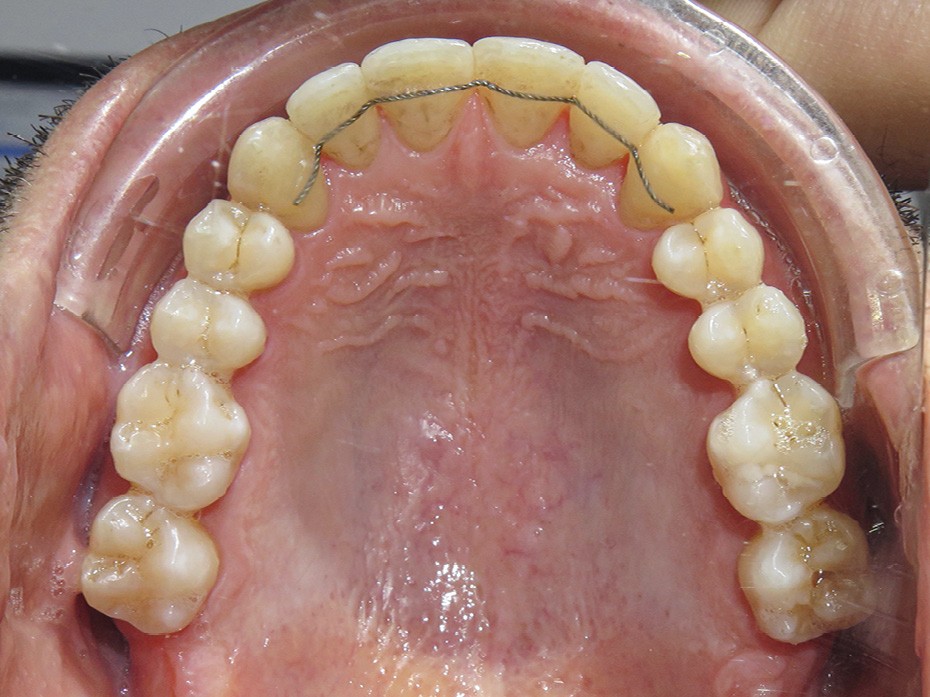

Dans un premier temps (fig. 2), la 28 (et la 18) a été extraite pour faciliter le déplacement de la 27 (DDM postérieure). Une minivis palatine a été placée entre 26 et 27 et des boutons ainsi qu’un sectionnel collés sur les faces vestibulaires des 26 et 27. Des chaînettes élastomériques ont été ancrées sur les boutons et la minivis, en passant au-dessous des faces occlusales de ces dents. Les chaînettes reliant un dispositif vestibulaire et un palatin et prenant appui sur les faces occlusales des molaires du secteur 2, les mouvements dentaires induits sont un déplacement vestibulo-palatin associé à une ingression des 26 et 27. Les minivis sont des ancrages absolus qui ne nécessitent pas d’utiliser l’ancrage des dents adjacentes ou antagonistes, ce qui préserve d’effets sur ces dernières.